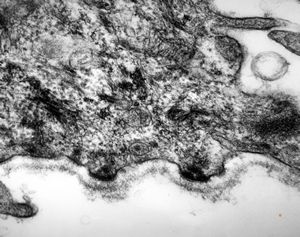

normal seromucinous salivary gland